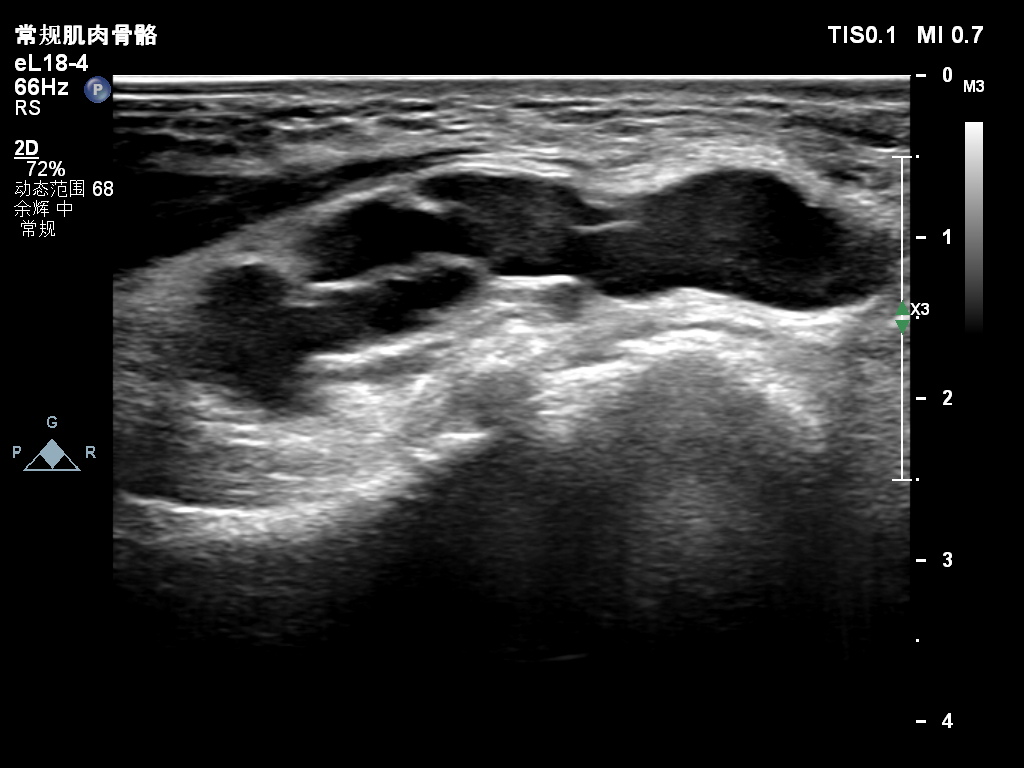

超声所见:右侧尺神经于肘管上段增粗,较粗处横截面积约0.25cm²,神经外膜及神经束膜显示欠清晰,神经纤维连续性可。尺神经走行至肘管处受压变扁,局部尺神经外膜处可见囊性结构并向肘管远段延伸,边界清,形态不规则,内可见多条带状分隔。CDFI:囊性结构内未见明显血流信号。

2:右侧肘管处尺神经外膜囊肿——考虑神经鞘囊肿

肘管段及肘管远段尺神经外膜囊肿